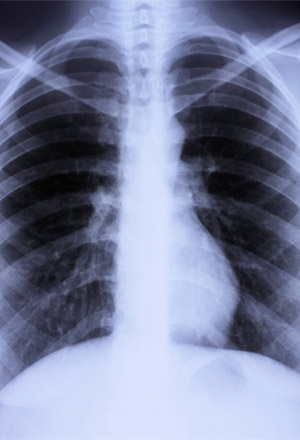

If you need a diagnostic x-ray, don't forget to let your healthcare provider know that you are pregnant, says Edwards. Although it is generally safe and the risks are low, experts often recommend that pregnant women postpone getting unnecessary X-rays until after giving birth. The level of safety depends on the type of X-ray you need and exactly how much radiation you're going to be exposed to. If the x-ray doesn't involve the abdomen, there is the possibility of using lead aprons to protect the fetus.